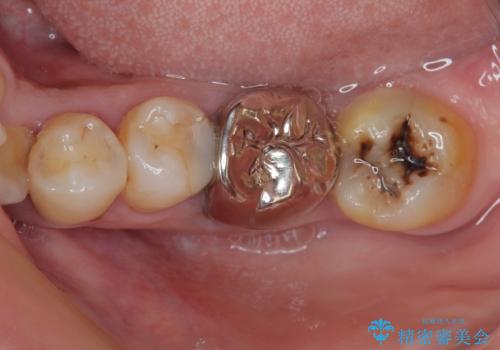

下顎大臼歯の再根管治療とオールセラミッククラウンによる補綴治療